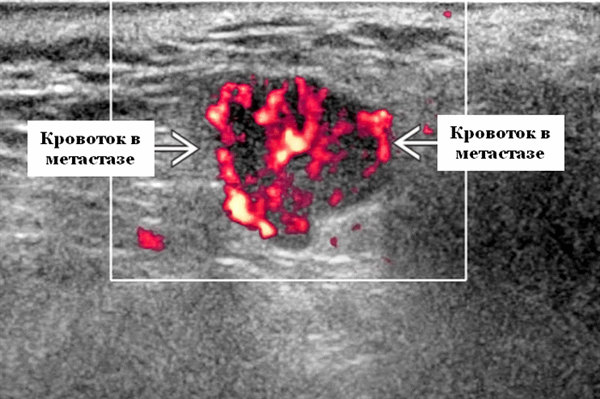

- Интранодулярный кровоток хаотичный / дезорганизованный или преимущественно периферический

Энергетический допплер. Внутриочаговая васкуляризация. Хаотический / дезорганизованный или преимущественно периферический кровоток

Визуализация. Общие особенности. Само по себе ультразвуковое сканирование метастазов в околоушные лимфоузлы неспецифична. Одиночные или множественные околоушные образования. Хорошо выраженный или плохо выраженный лимфоузел (экстранодальное распространение), однородный или неоднородный с внутренним некрозом. На УЗИ с ЦДК внутриузловая васкуляризация или усиление кровотока. Патология связана с известным первичным раком, часто в прилегающей коже или региональной области головы и шеи. Околоушные и перипаротидные узлы: узловая станция 1-го порядка при плоскоклеточной карциноме кожи (ПКК) и меланоме латеральной части волосистой части головы, ушной раковины / наружного слухового прохода и передней части лица